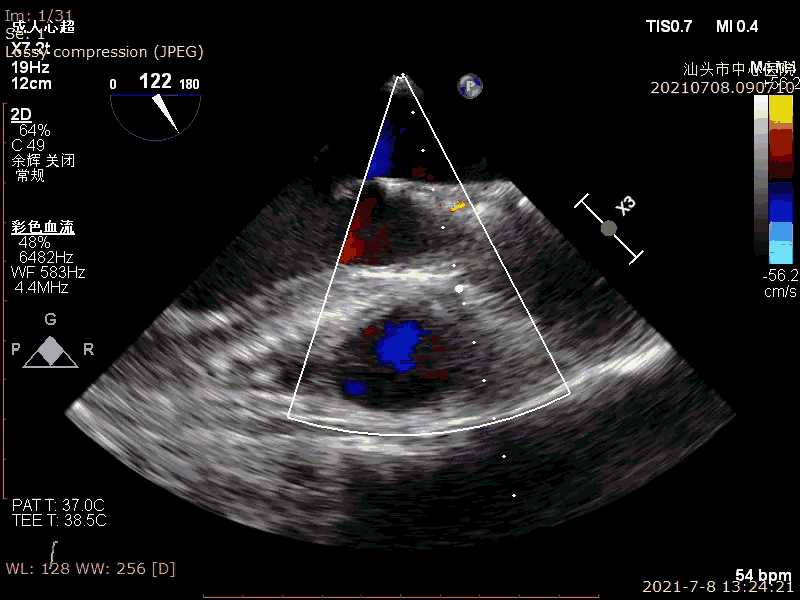

超声示:

LVEF:63%

重度主动脉瓣狭窄并轻度反流

术前超声

术后超声